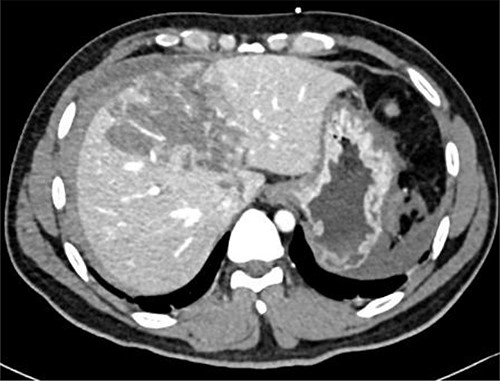

Resuscitation was carried on with 2 l of normal saline and two PRBC units to stabilize the patient. The computed tomography (CT) scan identified Grade 4 liver injury with hemoperitoneum (Fig. 2). Subsequently, the multiple bone fractures underwent surgical fixation, and post-operatively, he was hemodynamically stable. On the fifth day after admission, repeated CT scan demonstrated the liver injury with no evidence of hepatic pseudoaneurysm (Fig. 3). The patient remained stable with tolerated feeding with no abdominal pain or distension. On the Day 17, he developed abdominal pain mainly in the epigastrium, which was associated with nausea and deep epigastric tenderness. Abdominal ultrasound (US) (Fig. 4) and CT scan (Fig. 5) revealed complex, large intraparenchymal hepatic pseudoaneurysm (measuring about 58 × 41 × 30 mm) related to the left hepatic artery Segment 4 branch with surrounding hematoma located mainly at segment 4B/A ,and there was another tiny pseudoaneurysm seen at Segment 4A. Selective angiography confirmed the diagnosis of pseudoaneurysm with multiple blood supplies from Segment IV and Segment II.

Contrast-enhanced CT scan revealing a right hepatic artery pseudoaneurysm in the right lobe of the liver.

Embolization was achieved using gel foam and particle (embosphere: 100–300 mic) through microcatheter until satisfactory stagnation of forward flow was reached and back flow was seen. Then, the aneurysm was occluded with placement of six microcoils (3 and 5 mm) (Fig. 6).